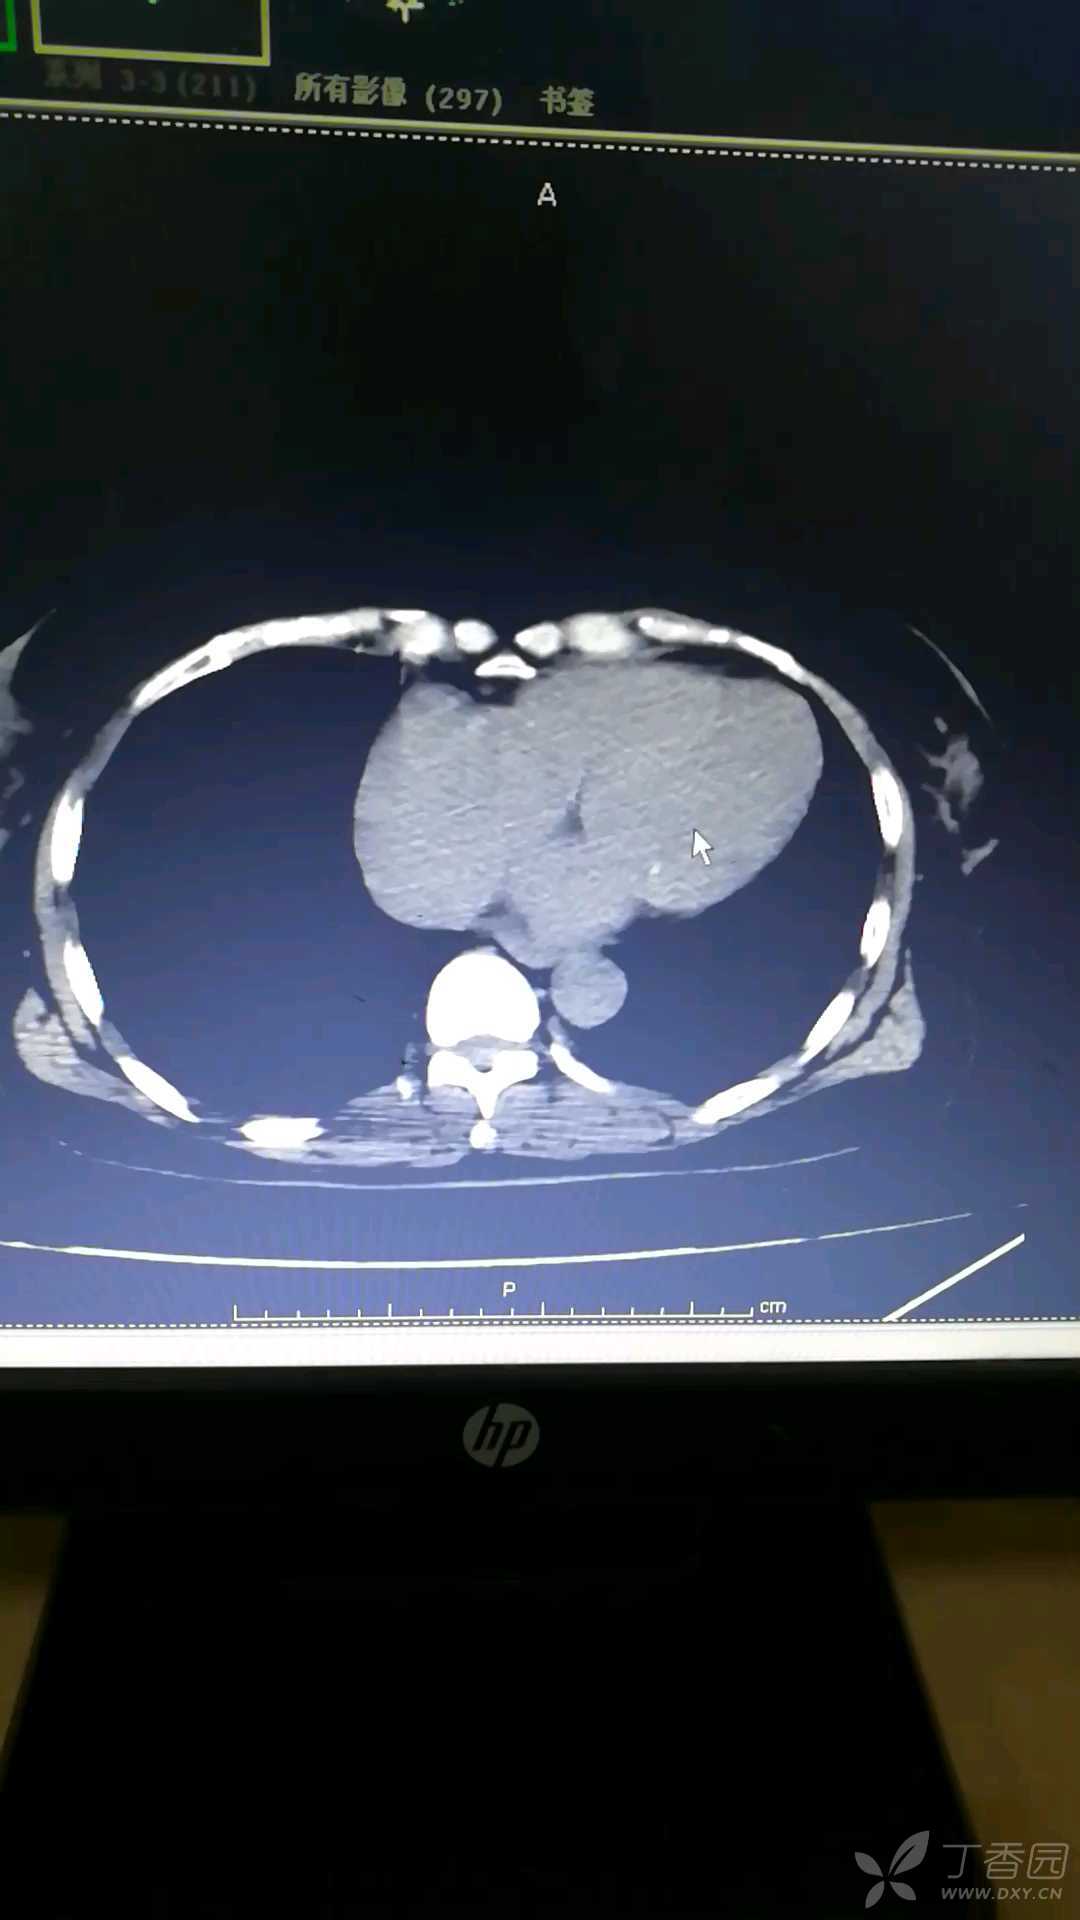

出现图示的表现.提示病人出现了

图片尺寸480x309